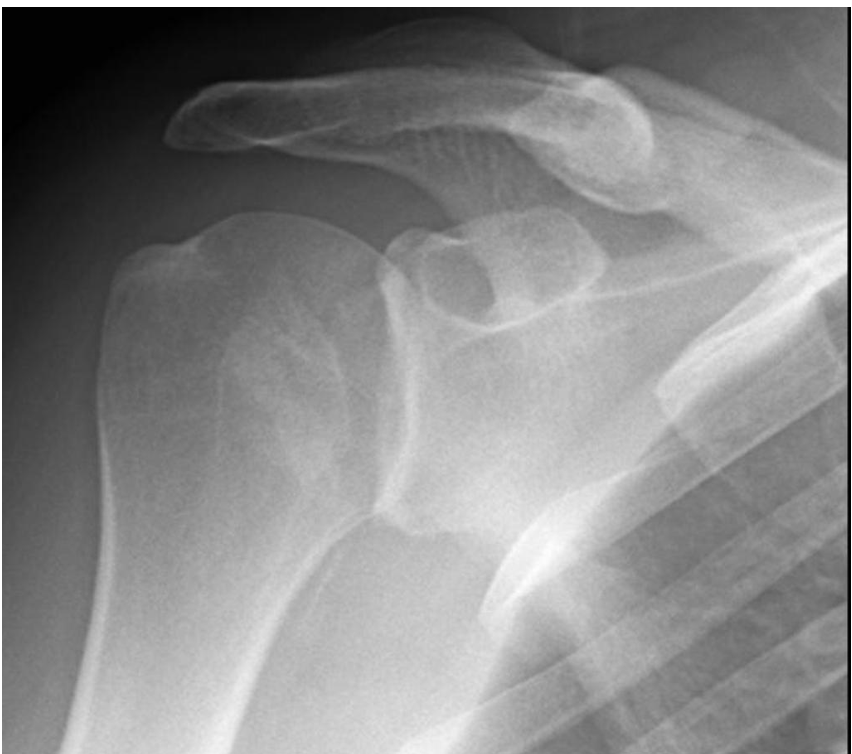

Luxation ant ou postérieure?

Vue axillaire de l'épaule

Vous faites des rayons-X de l’épaule droite chez cette patiente. Il s’agit d’une vraie AP de Neer. Qu’est-ce que ce RX démontre?

A

Luxation postérieure de l’épaule.

Il y a superposition de la tête humérale et de la glénoïde sur la vue AP de Grashier

# Voyez-vous une luxation sur cette AP de Neer gléno-humérale?

oui ## Footnote superposition tete humerus et glénoide